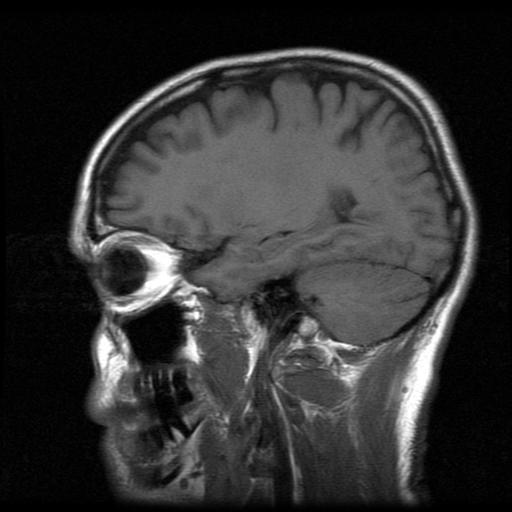

Enfermedad de Pick

La enfermedad de Pick es una demencia progresiva que se caracteriza por cambios en el comportamiento y en la personalidad. Las consecuencias de esta enfermedad afecta las habilidades sociales, la inteligencia y la memoria. Su inicio es progresivo, y es común en personas de 50 a 60 años. En la actualidad aún no se han encontrado tratamientos para dicha enfermedad,  pero tiene un pronóstico poco alentador. A continuación, te presentaremos, cómo detectar la enfermedad de Pick.